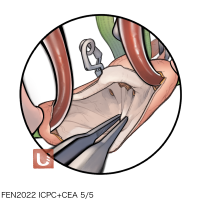

FEN2022シリーズ